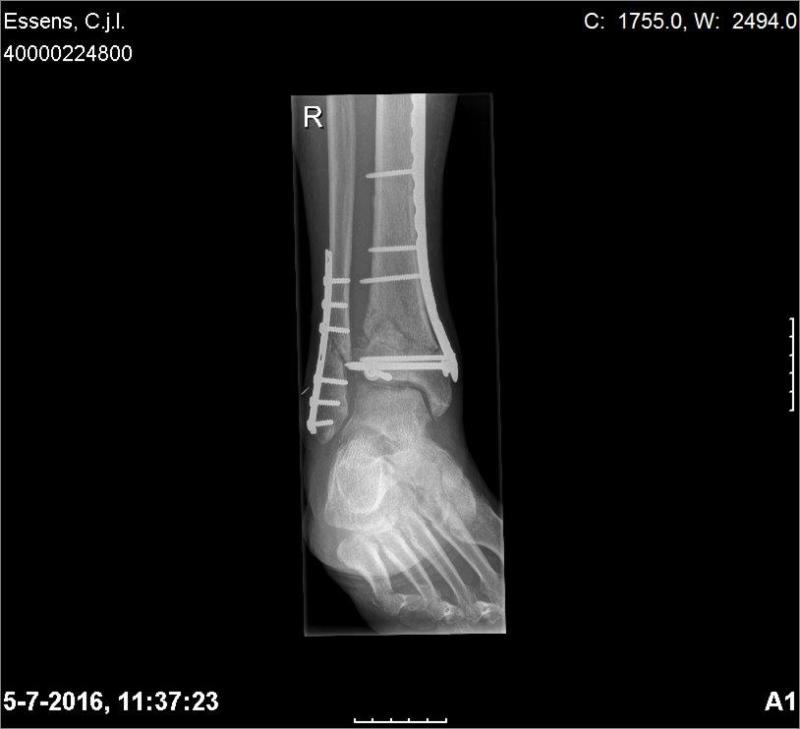

Dr. Eggen was zeer verrast, de breuklijn in het kuitbeen is al bijna weg. In het scheenbeen is de botdichtheid al veel beter. Er beginnen zich lijnen te vormen. Het verschil tussen de 2 foto's is ruim 3 mnd. De peptides werken goed. In april gaan de platen eruit, dat is standaard bij jonge mensen...haha

Bron: Bosco's Ongeval